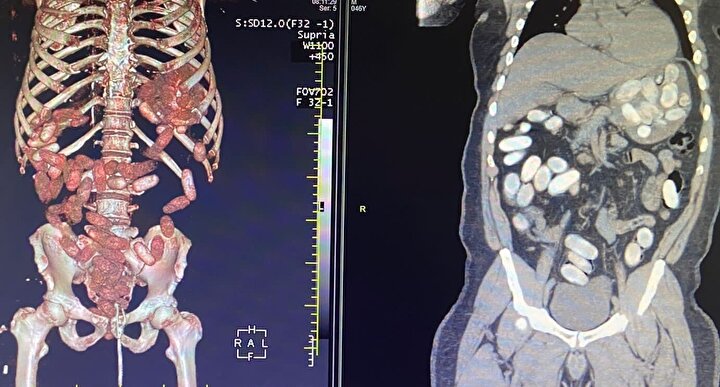

Gümrük Muhafaza ekiplerince savcılık talimatı doğrultusunda detaylı bilgisayar tomografi çekilmesi için sağlık kuruluşuna götürülen 6 yolcunun yapılan tarama ve muayenelerinde, 761 adet ve toplam ağırlığı 10 kilo 420 gram kokain tespit edildi.

İkinci operasyonda, başka yolcunun da 'yutucu' kurye olduğu bilgisine ulaşan ekipler, şüpheliyi takibe aldı. Yolcuda, 'yutucu' tespit cihazı ve ardından sağlık kuruluşunda yapılan muayene sonucu 48 adet kapsül ve toplam ağırlığı 760 gram kokain ele geçirildi.